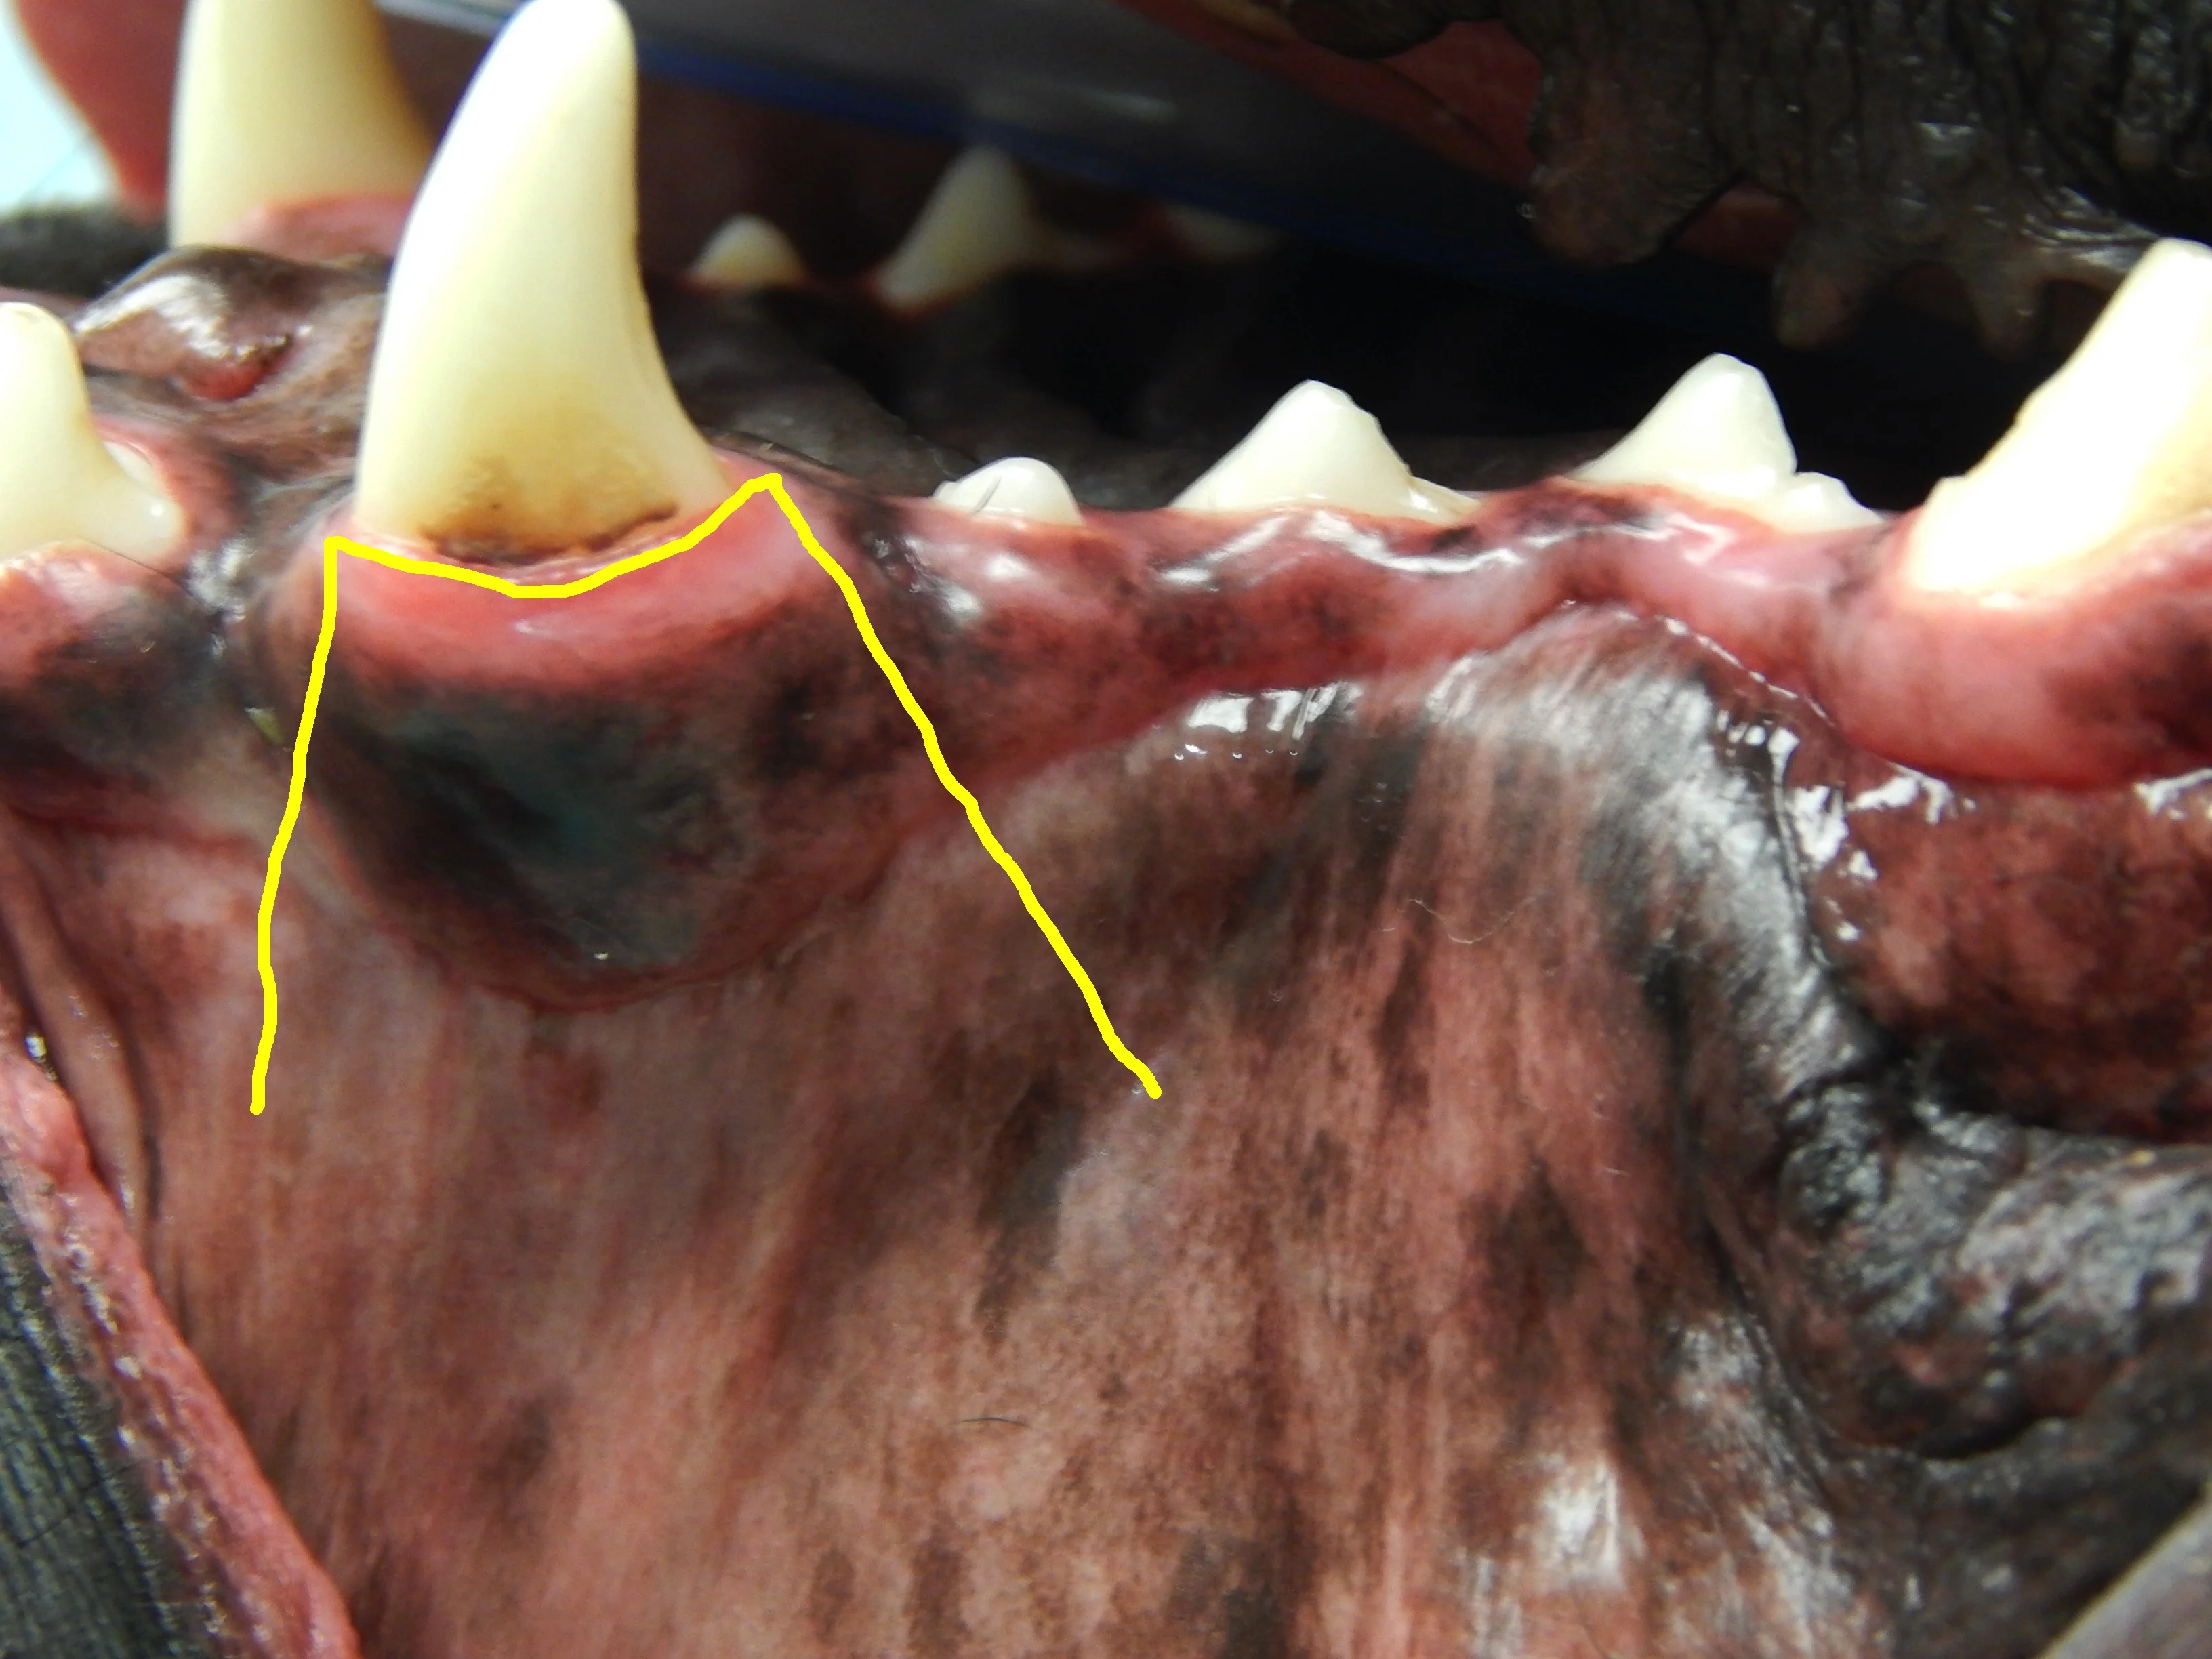

Closing a mucogingival flap under tension increases the risk for dehiscence,4 and understanding the options available for complete flap mobilization (eg, proper release of the periosteum, preplanning advancement flap design, releasing incision placement) is important when reducing tension on a flap. Damaged tissue should be removed prior to closure of the wound. Patients with severe periodontal disease can have significant loss of the buccal-attached gingiva and mucosa (Figure 3). Tissue that is lost, either due to pre-existing disease or surgical trauma, makes closure of a gingival flap more difficult.

Calculus accumulation and significant loss of the attached gingiva (arrows) of the left maxillary canine tooth. Gingival recession can make surgical closure more difficult and increase the potential for postoperative complications.